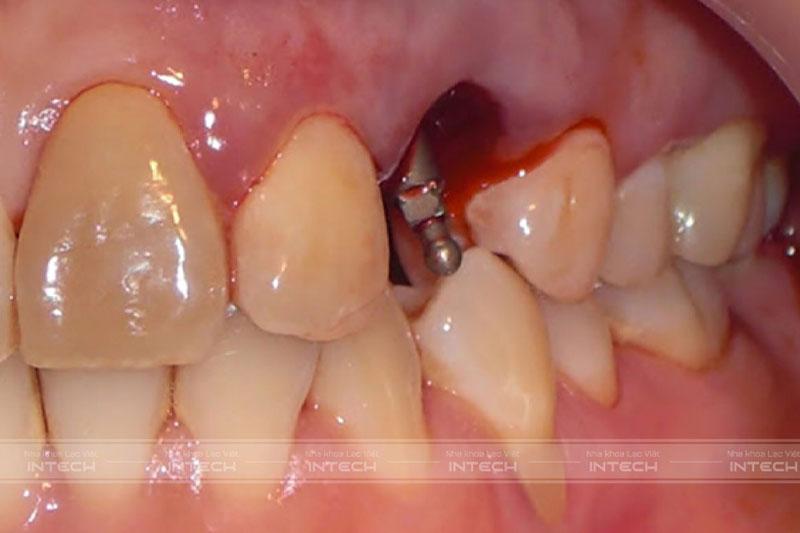

Biến chứng chảy máu kéo dài

Biến chứng cắm Implant đầu tiên là chảy máu kéo dài

Sau khi cấy ghép Implant, bệnh nhân sẽ thấy hiện tượng rỉ máu tại vị trí phẫu thuật. Đa phần các trường hợp trên là hậu quả của trồng răng Implant tuy nhiên chảy máu sau cấy ghép Implant thường ít trầm trọng và có thể dễ dàng cầm máu sau 1 - 2 ngày đầu. Tuy nhiên, nếu như tình trạng chảy máu kéo dài quá 3 ngày hoặc không thể cầm máu thì bệnh nhân cần liên hệ với bác sĩ để được kiểm tra và xử lý kịp thời.

Trong miệng có những cấu trúc giải phẫu là mạch máu nguy hiểm. Nếu bác sĩ phẫu thuật không nắm vững kiến thức hoặc thiếu kinh nghiệm thì có thể làm tổn thương các mạch máu trong quá trình phẫu thuật. Điều này sẽ dẫn tới biến chứng chảy máu kéo dài sau cấy ghép Implant.